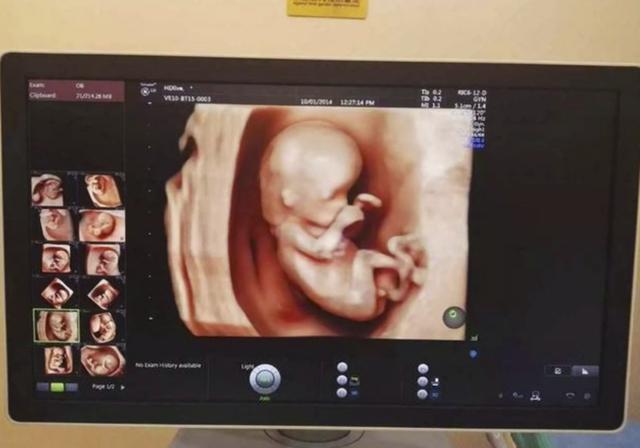

临床上,有一半的孕妇会查出胎位不正,胎位就是胎儿在子宫里的位置,有头位、臀位、横位三种胎位,一般以怀孕30周为一个临界点,怀孕30周后还不正常的体位就叫胎位不正。

头位:胎儿的头在下面,屁股在上面的就叫头位,分娩时胎头先出来;

臀位:与头位刚好相反,屁股在下面,头在上面的胎位;

横位:胎儿在子宫里平躺着,与妈妈的身体相互垂直的就叫横位。